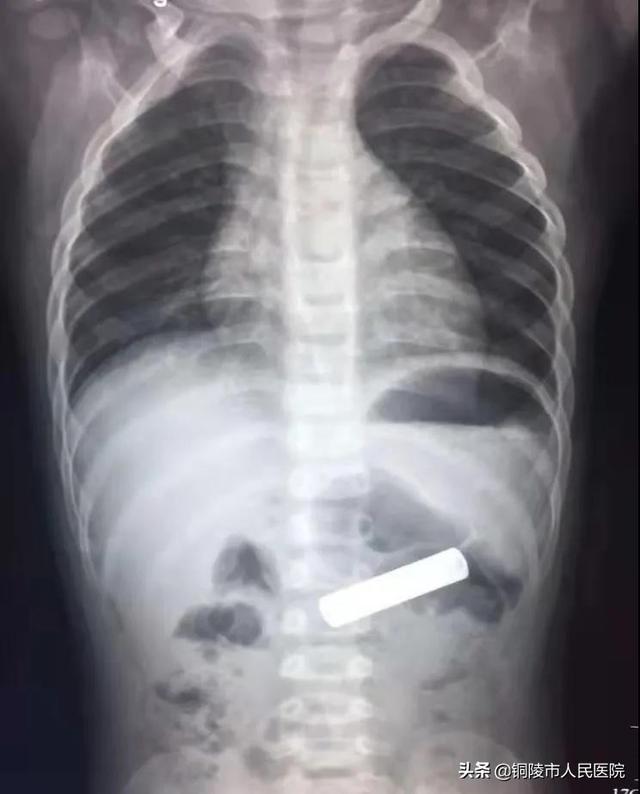

经X线检查,确认患儿胃内有一长条状异物,与电池形状相符。

经过一系列的术前准备,Stedenggao医生花了不到十分钟's时间给顺利取出,,做了电池,父母再三感谢他!